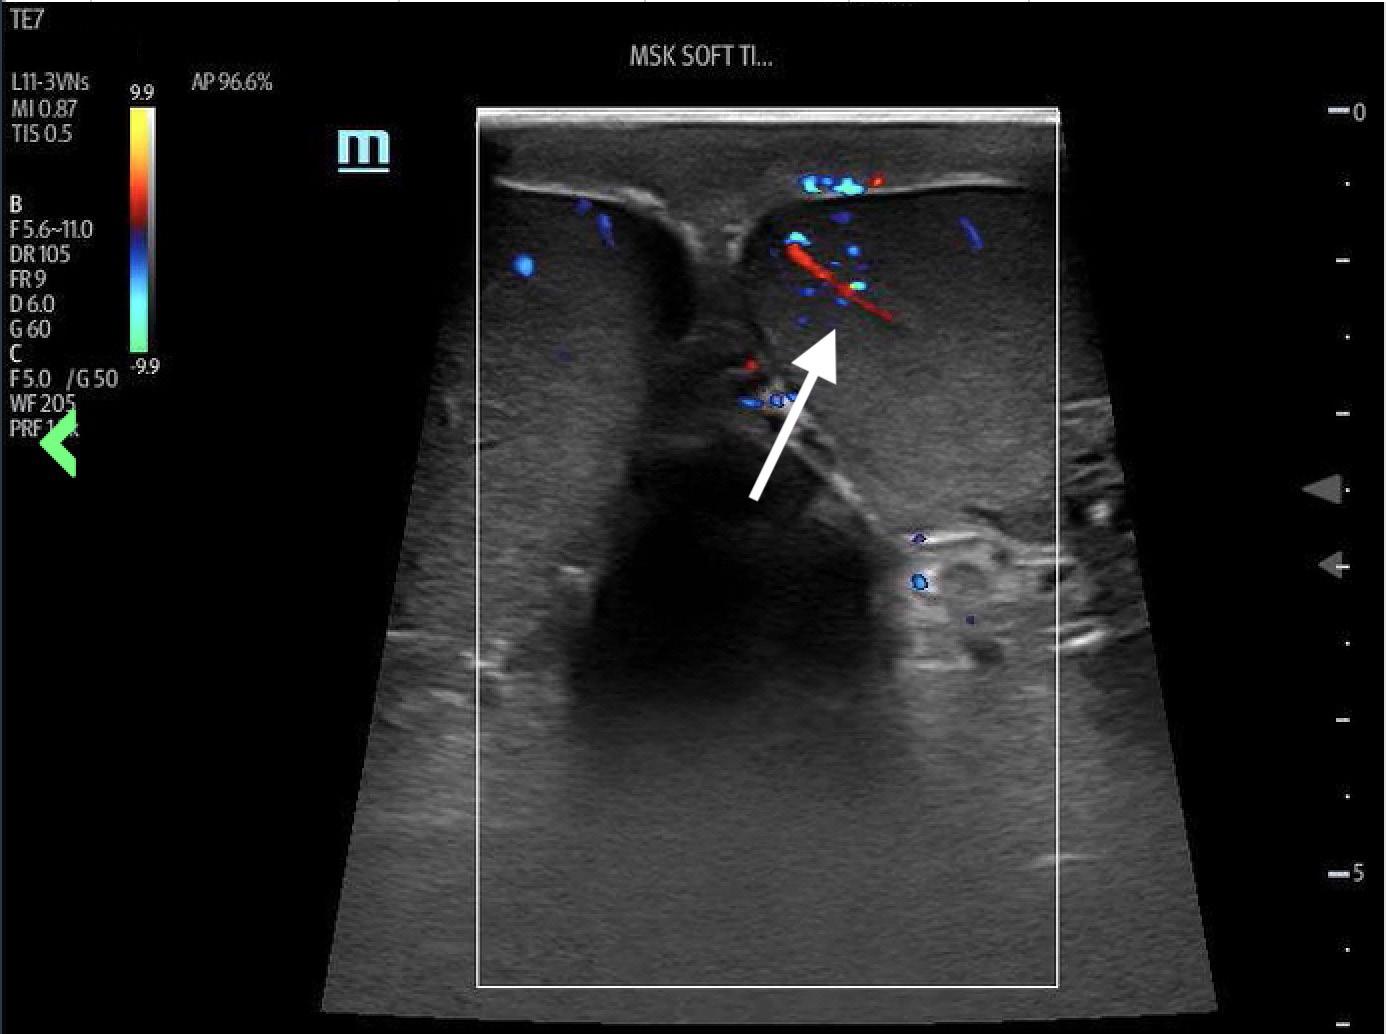

overload from RVOT obstruction (Image 3). Pulmonary ultrasound revealed a normal A-line pattern, and POCUS

Image 3. Parasternal short-axis view of the heart notable for interventricular septal flattening (*) due to right ventricular pressure overload in the setting of right ventricular hypertrophy (arrow). LV, left ventricle; RV, right ventricle.

Video 2. Interventricular septal flattening due to right ventricular pressure overload (*); right ventricular hypertrophy (arrow); left ventricle (LV) right ventricle (RV).